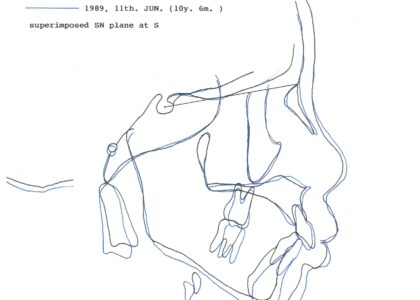

- セファロ